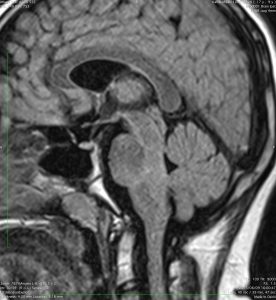

7歳女児です,発熱の後で右外転神経麻痺が生じました。その後,左外転神経不全麻痺。翌年に,軽度の嚥下障害,嗄声,軽度の四肢失調が出現しています。その翌年8歳時にMRIにて脳幹部病変を発見されています。両側瞳孔散大,右顔面神経麻痺,体感失調など加わり,DIPGの診断で54グレイ27分割の放射線治療を受けました。照射中2週間くらいで症状の進行が止まり,改善傾向となりました。照射終了時には脳幹病変は著しく縮小しました。

これはDIPGでしょうか? 中脳被蓋,橋被蓋,延髄が腫大しています。右下中脳脚の腫大と延髄の肥大が目立ちます。逆に脳橋腹側の腫大は軽度です。拡散強調は等信号でガドリニウム増強されません。壊死やのう胞形成は認められません。DIPGとしては,橋底部の異常信号が軽度なことが非典型的です。びまん性橋膠腫と呼ばれますが,橋の信号がびまん性ではありません,DIPGの特徴であるhomogenous high-signalがないのです。DIPGは延髄から中脳まで進展することは多いのですが,びまん性に連続性にmass effectを有して連続性腫瘍性病変となるものです。逆にまだらな高信号になっています。

治療後半年のMRIです。病変はほぼ完全に消失しています。右外転神経麻痺(後に矯正手術しました)のみを残し,マラソンもできるくらいに症状は回復し,発症後10年以上になりますが,普通に通学しています。この例では,感染による亜急性の脳幹脳炎 localized brain enchephalitisや感染後脳症 (ADEM)などが疑われるのかもしれません。もしかして,ステロイド治療をまず使用してみるべきだったのかもしれません。